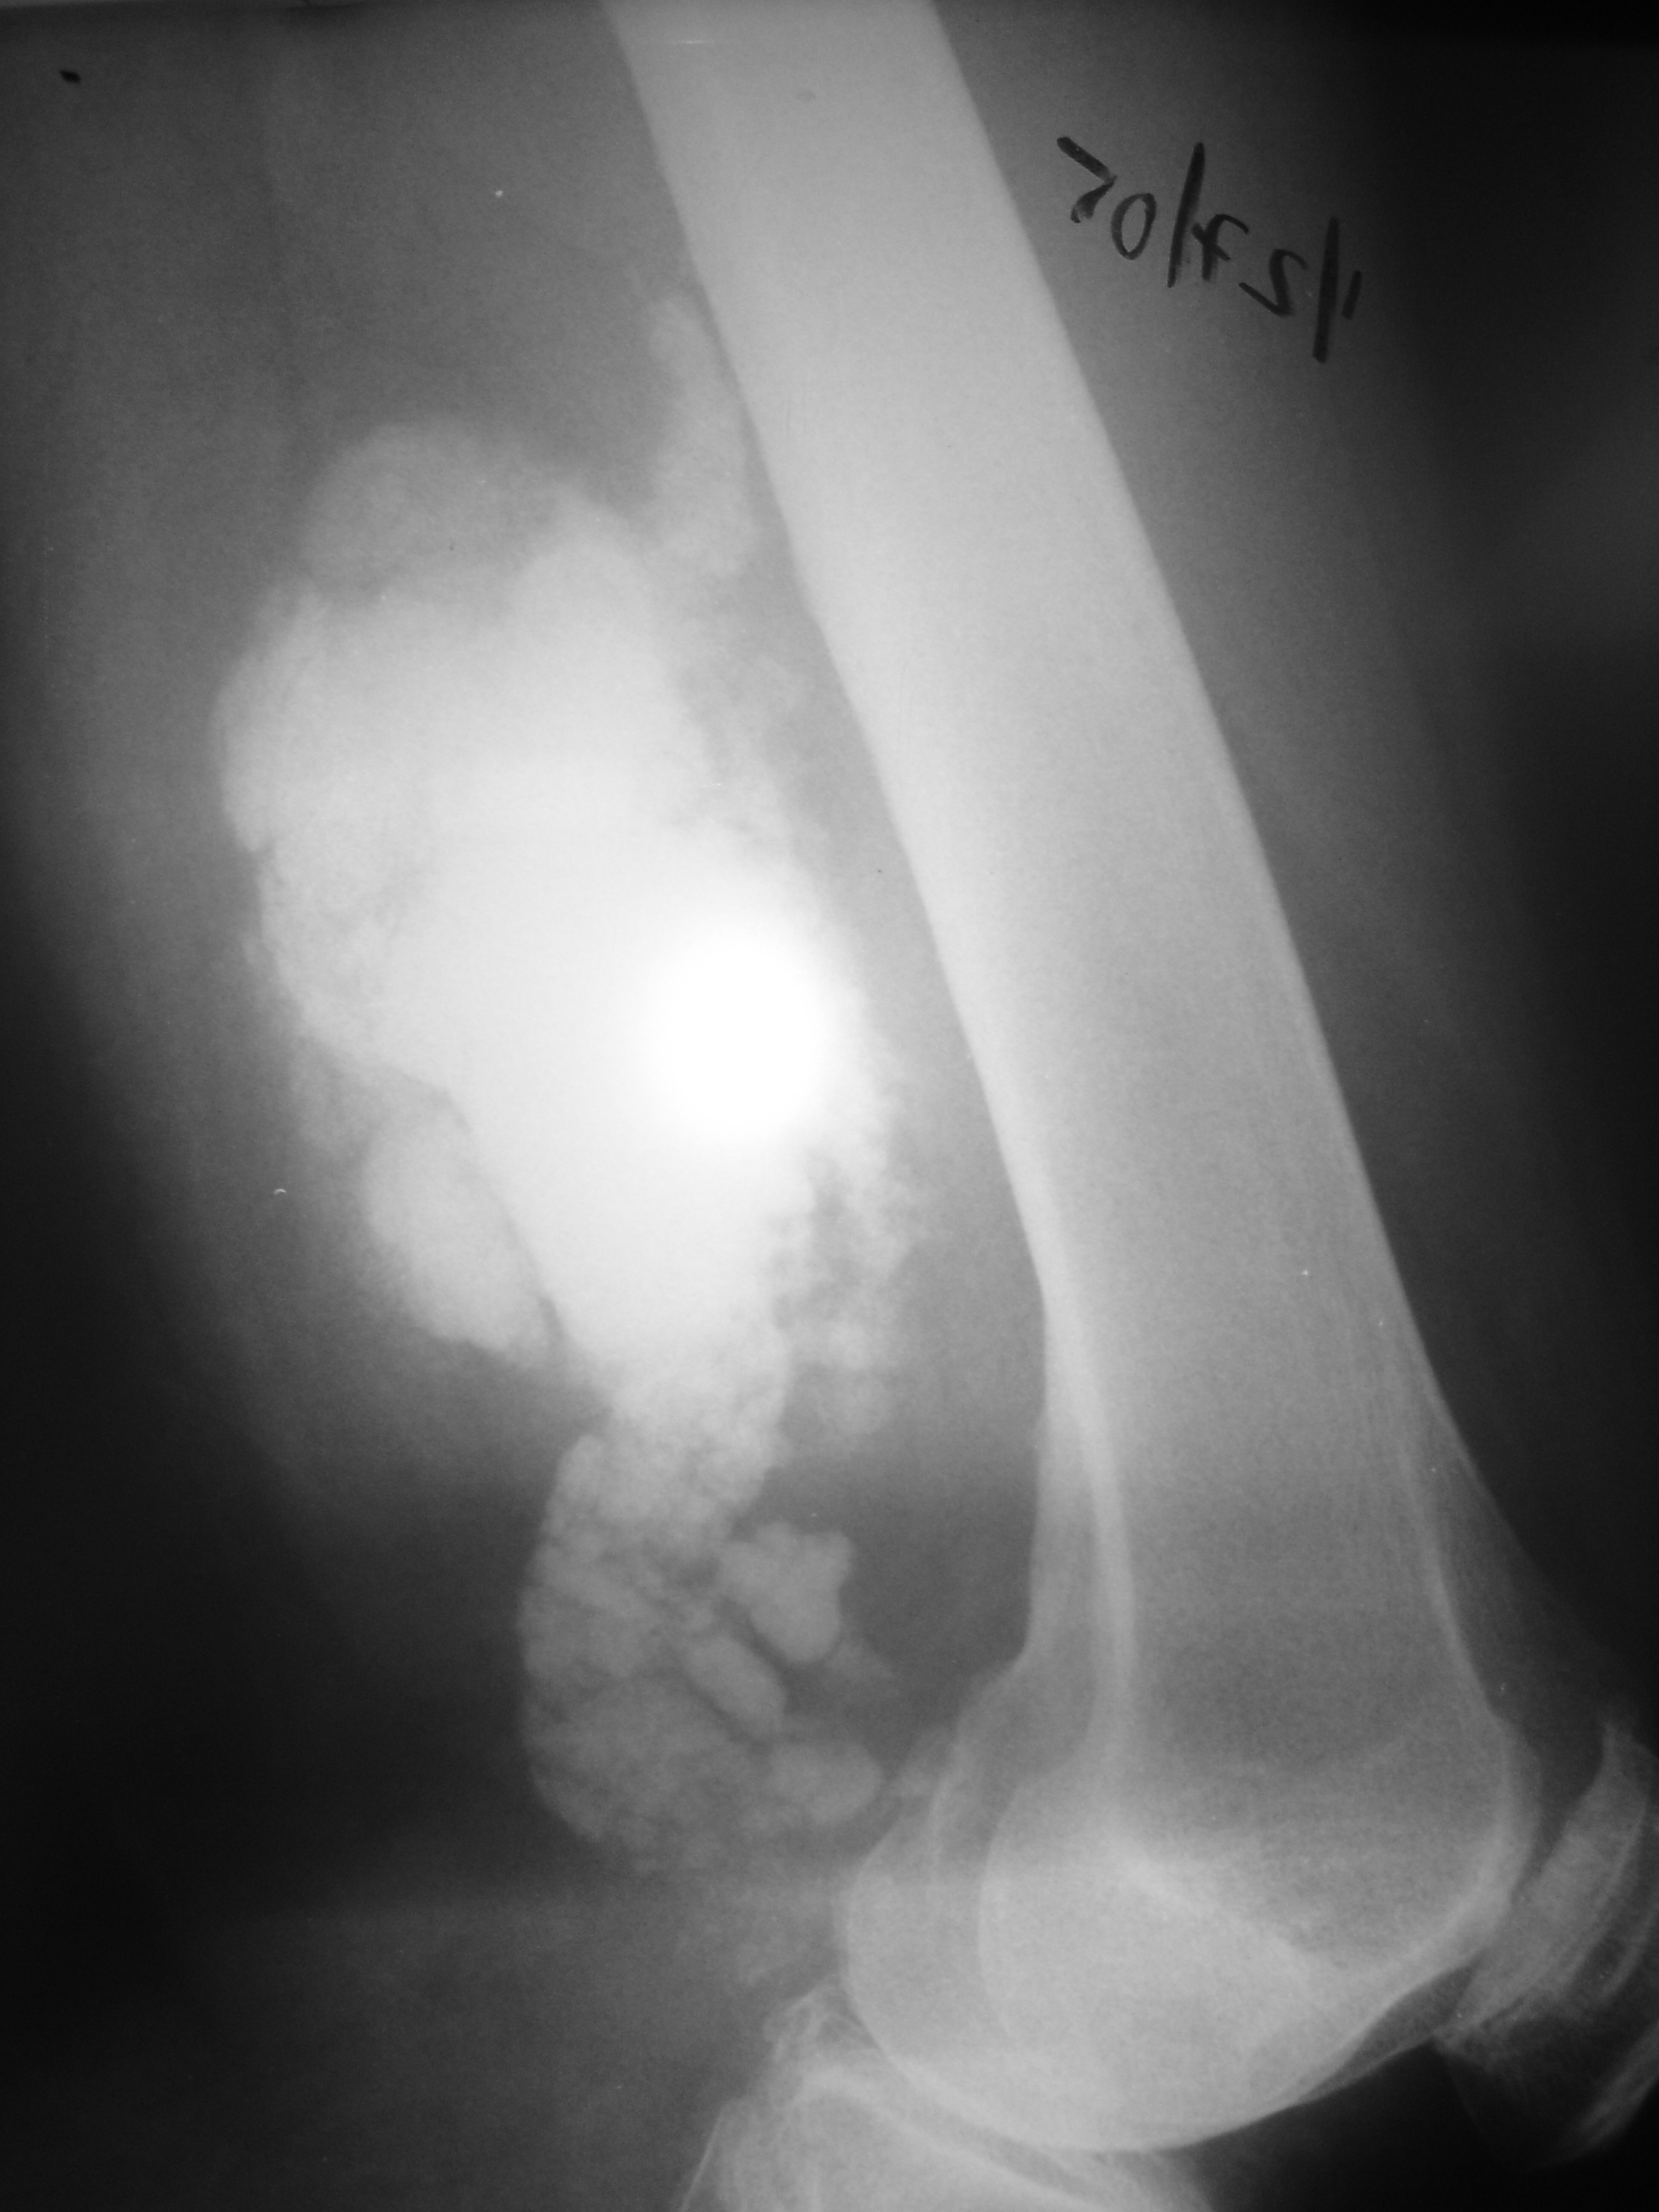

Osteochondroma Page ( 1 ) - AAOS - OrthoInfo

Show the bony growth of an osteochondroma. Other imaging scans. Doctors may also request computed tomography (CT) scans Osteochondroma cont. Several tumors in the femur and tibia are apparent in this x-ray of a child’s knee taken from the side..org ... Return Document

Malignant Fibrous Histiocytoma Of Bone: Conventional X-ray ...

Tumors were most frequently located in the appendicular skeleton (Table 1). Only eight of the 39 tumors (21%) Figures 2 and 3 show the typical X-ray features of MFH; lesions are osteolytic and show an aggressive growth with cortical destruction. ... Access Content